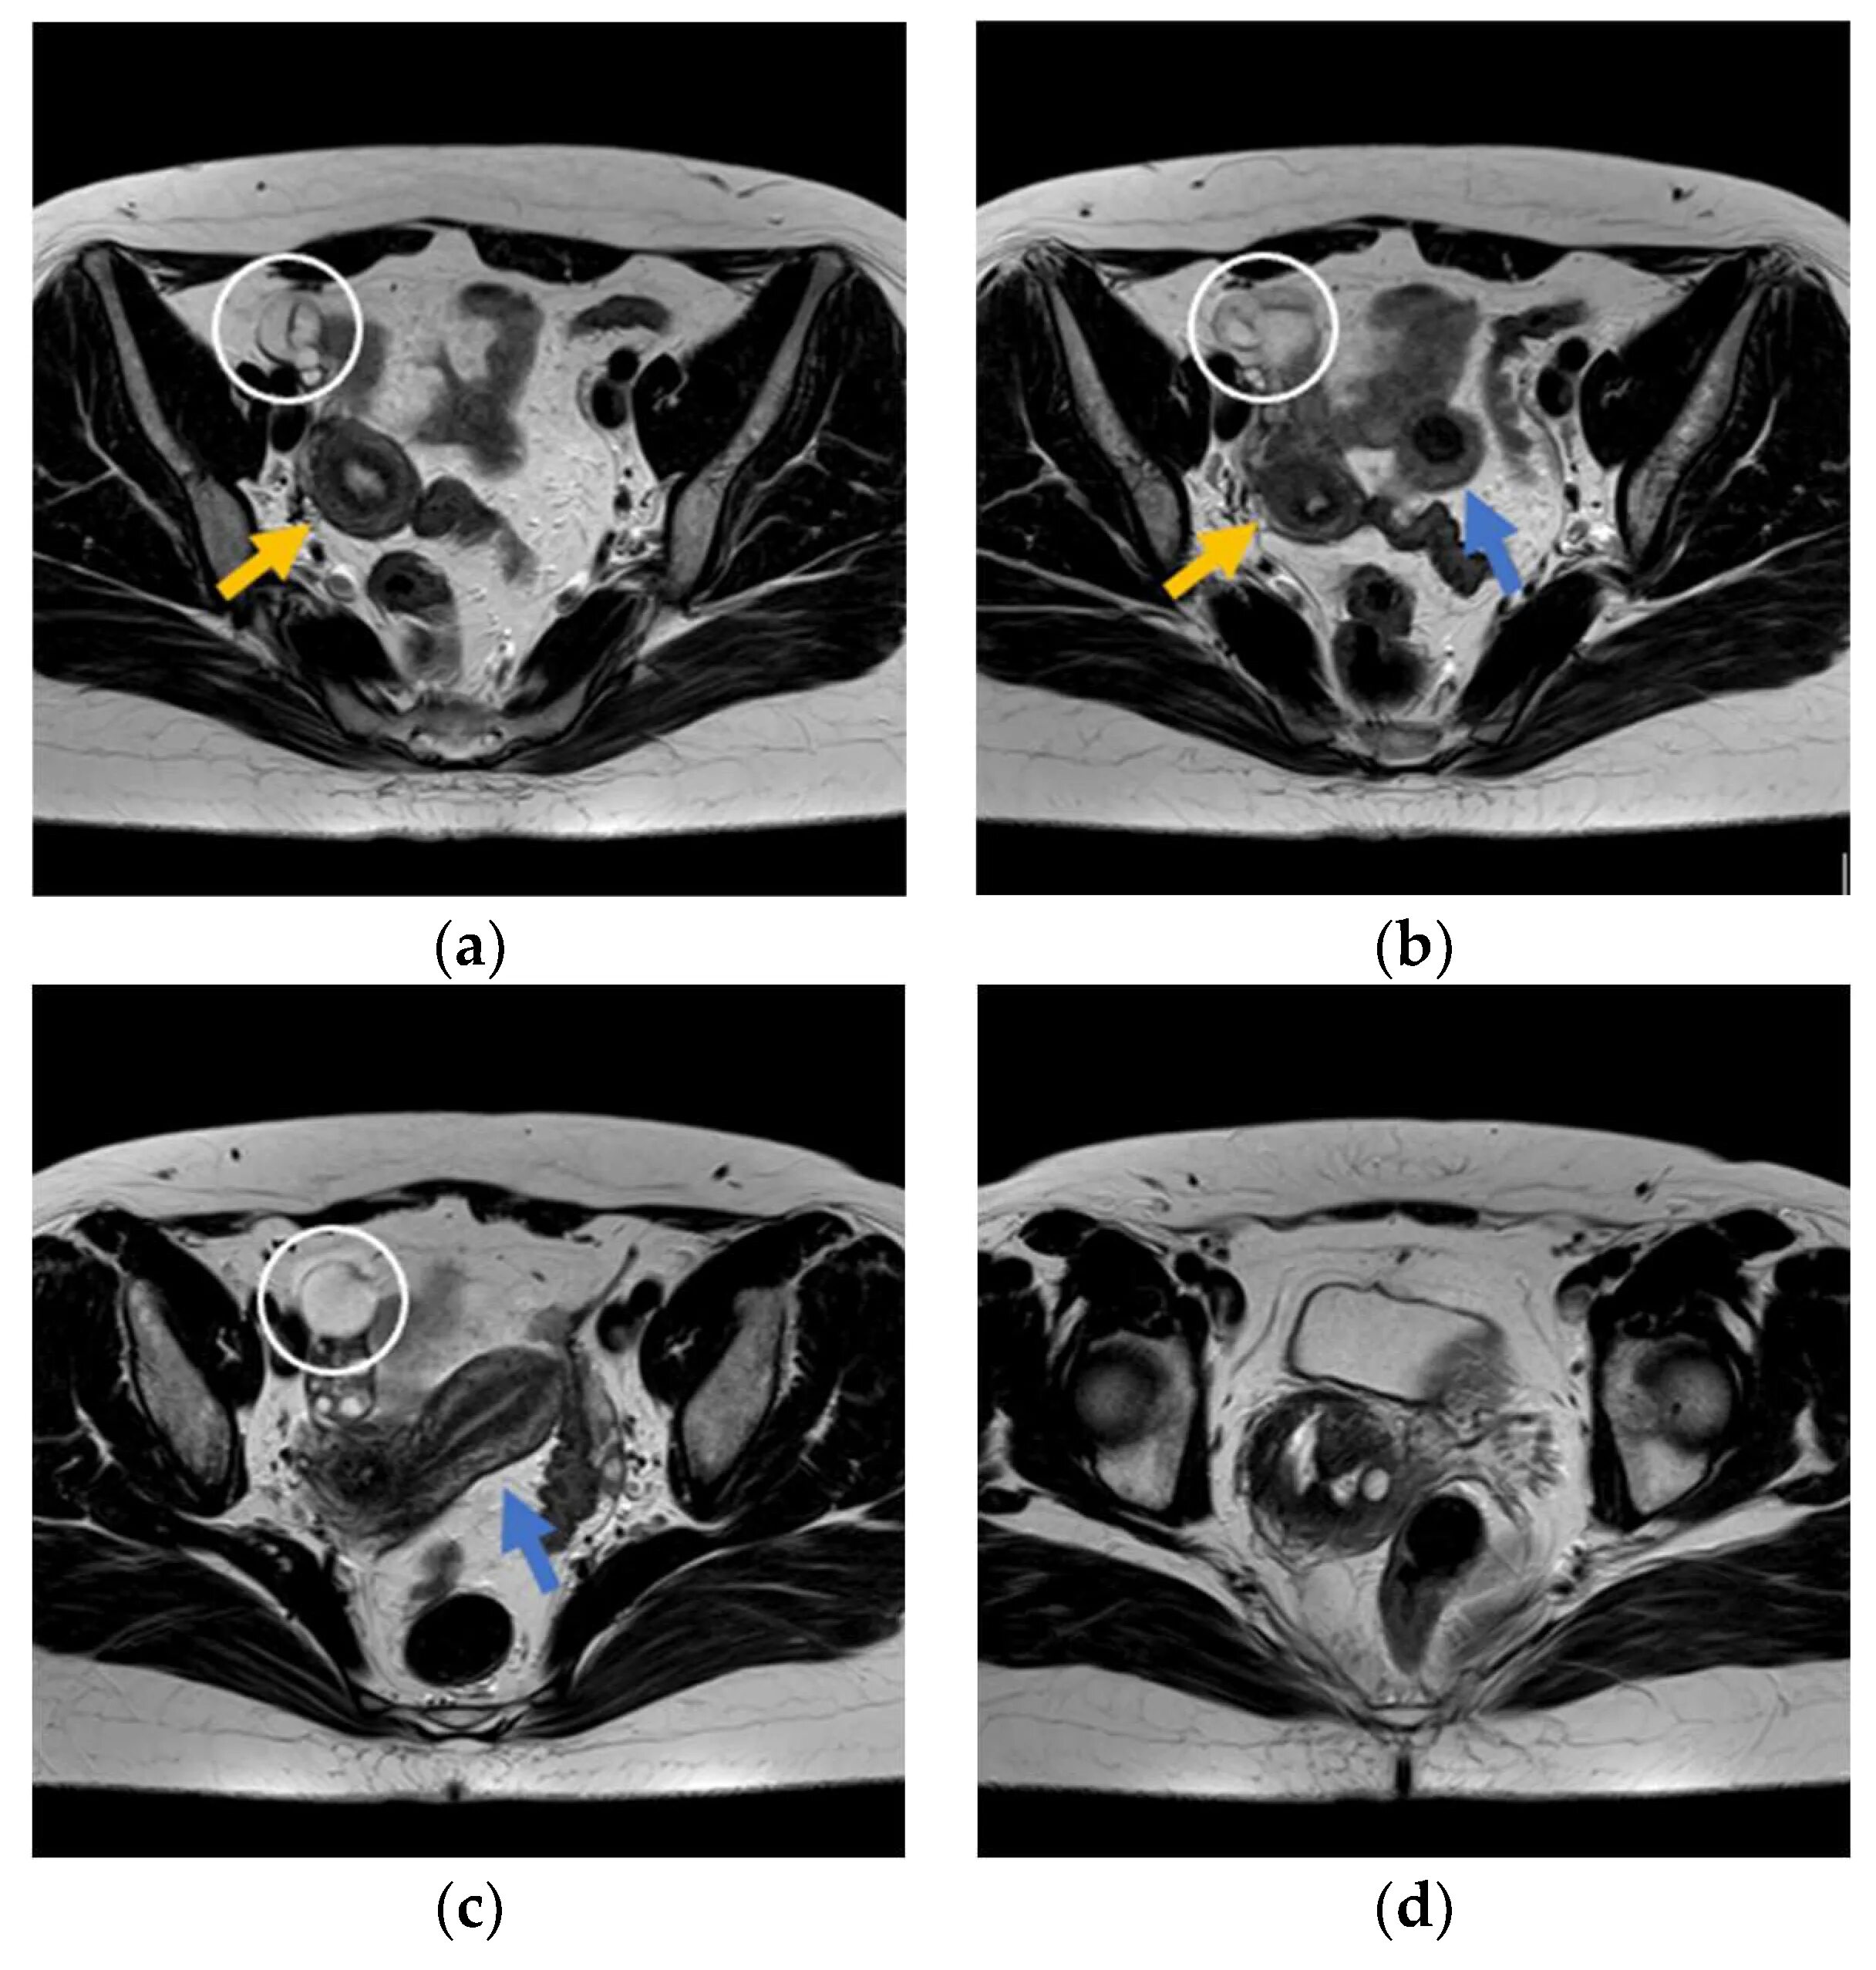

Гидросальпинкс что это такое как лечить